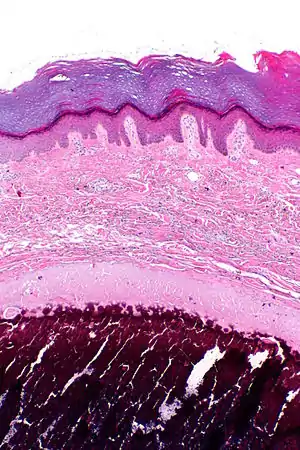

| Micrograph of calcinosis cutis. The calcification is purple (bottom of image). H&E stain. | |